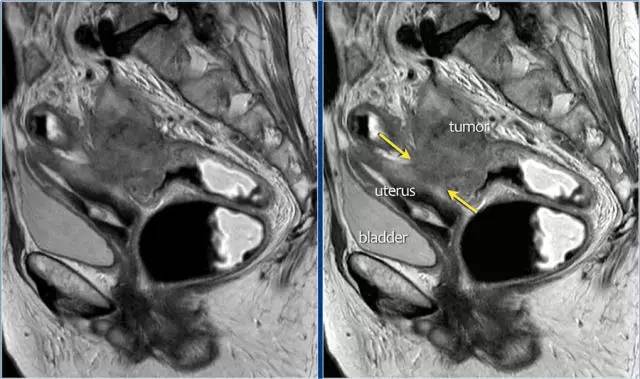

图 16 在矢状 T2W 图像上,直肠和阴道后壁之间有脂肪平面的损失。在轴向图像上,看到肿瘤的相对低的信号强度延伸到阴道的后壁(箭头)

图 17~21 肿瘤的低信号强度延伸到阴道的后壁(箭头)

图 22 浸润到子宫后壁的肿瘤